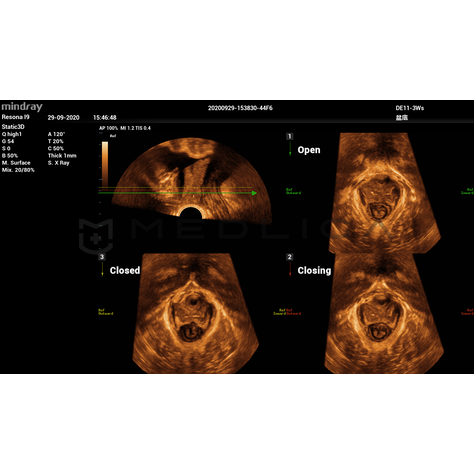

Программное обеспечение для автоматических измерений параметров и оценки функции мышц тазового дна.

Smart Pelvic - новое решение, позволяющее значительно упростить диагностическую процедуру и свести к минимуму время исследования функций мышц тазового дна. Благодаря чрезвычайно простому пользовательскому интерфейсу, программа генерирует стандартную систему координат и автоматически просчитывает все связанные измерения в течение нескольких секунд.